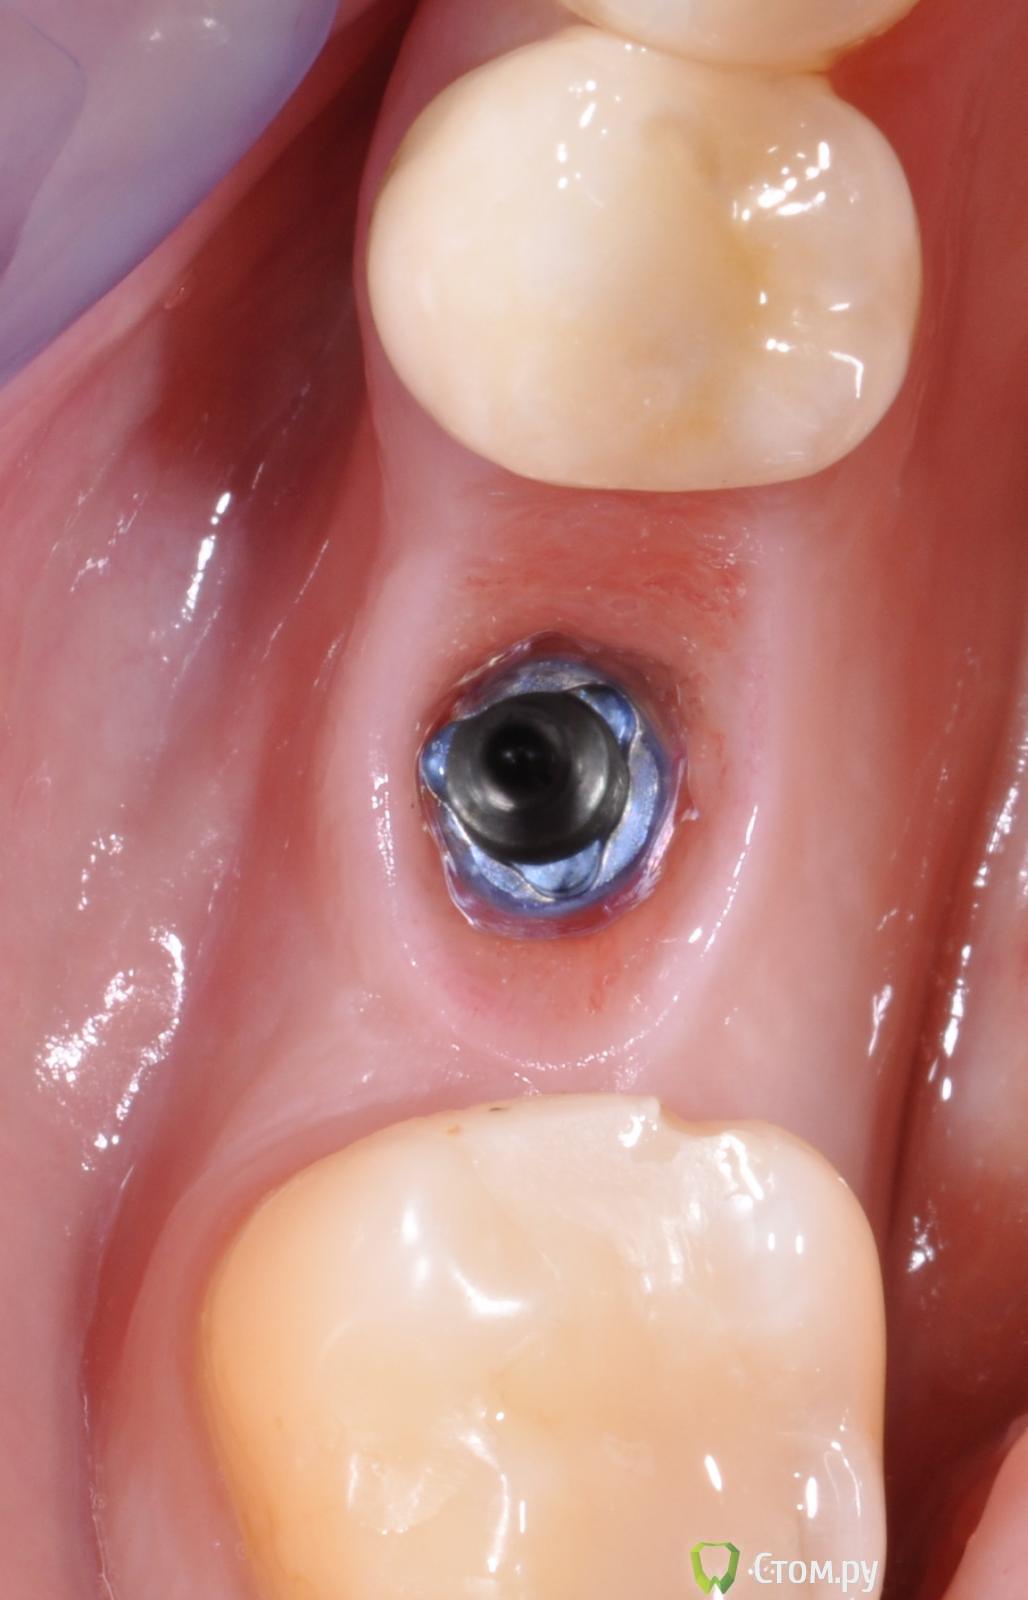

doctore Опубликовано 10 ноября, 2011 Поделиться Опубликовано 10 ноября, 2011 (изменено) ну эту картинку мы все видели ) хороший пример грамотных продаж ) Владислав, вы, как ментор Нобеля, наверняка сейчас активно начнете использовать новые имплантаты. Так вот, какая у вас будет форма абатмента на "нобель платформшифт" и "нобель ЦЦ" при установке Rp имплантата в дистальном отделе? Объем мягких тканей как раз таки легко создается десневой пластикой. Имплантолог,вероятно,крупно проигрался и задолжал.А тут две полные адентии откуда ни возьмись Согласен по поводу обьема и десневой пластики на 100%,но ведь в разумных пределах и при достаточной поддержке костной ткани(если она есть...Форма абатментов и результат,который я хочу видеть(это на Груви 4.3 и 5.0): Изменено 10 ноября, 2011 пользователем doctore Ссылка на комментарий

pit Опубликовано 11 ноября, 2011 Поделиться Опубликовано 11 ноября, 2011 (изменено) Имплантолог,вероятно,крупно проигрался и задолжал.А тут две полные адентии откуда ни возьмись Согласен по поводу обьема и десневой пластики на 100%,но ведь в разумных пределах и при достаточной поддержке костной ткани(если она есть...Форма абатментов и результат,который я хочу видеть(это на Груви 4.3 и 5.0): А Вы автор? И...... http://s42.radikal.ru/i096/1111/07/d9ba12a2a573.jpg Изменено 11 ноября, 2011 пользователем pit Ссылка на комментарий

doctore Опубликовано 11 ноября, 2011 Поделиться Опубликовано 11 ноября, 2011 (изменено) А Вы автор? И...... Пациентка одна-стороны разные.И хирургия и ортопедия мои. Изменено 11 ноября, 2011 пользователем doctore Ссылка на комментарий

r3yand Опубликовано 11 ноября, 2011 Поделиться Опубликовано 11 ноября, 2011 Док, а каким образом формировали профиль в данном кейсе?Явно ж не едиными фдм'ами)) Ссылка на комментарий

pit Опубликовано 11 ноября, 2011 Поделиться Опубликовано 11 ноября, 2011 Пациентка одна-стороны разные.И хирургия и ортопедия мои.Очень даже симпатично. Исходные условия тоже хорошие. Десну формировали апикальным смещением и временными коронками?Нагрузили имплантаты одномоментно ли вторым этапом? В свете Ваших приципов идеализации лечения, этот кейс выглядит не завершенным, позвольте пульнуть камушек в Ваш огород))))))))))))))))))))))) Почему Вы не сделали интрузию 26 зуба и не установили имплант в позицию 27 зуба? ( спрашиваю как ортопед) А вобщем работа понравилась и врачебное, и техническое исполнение Ссылка на комментарий